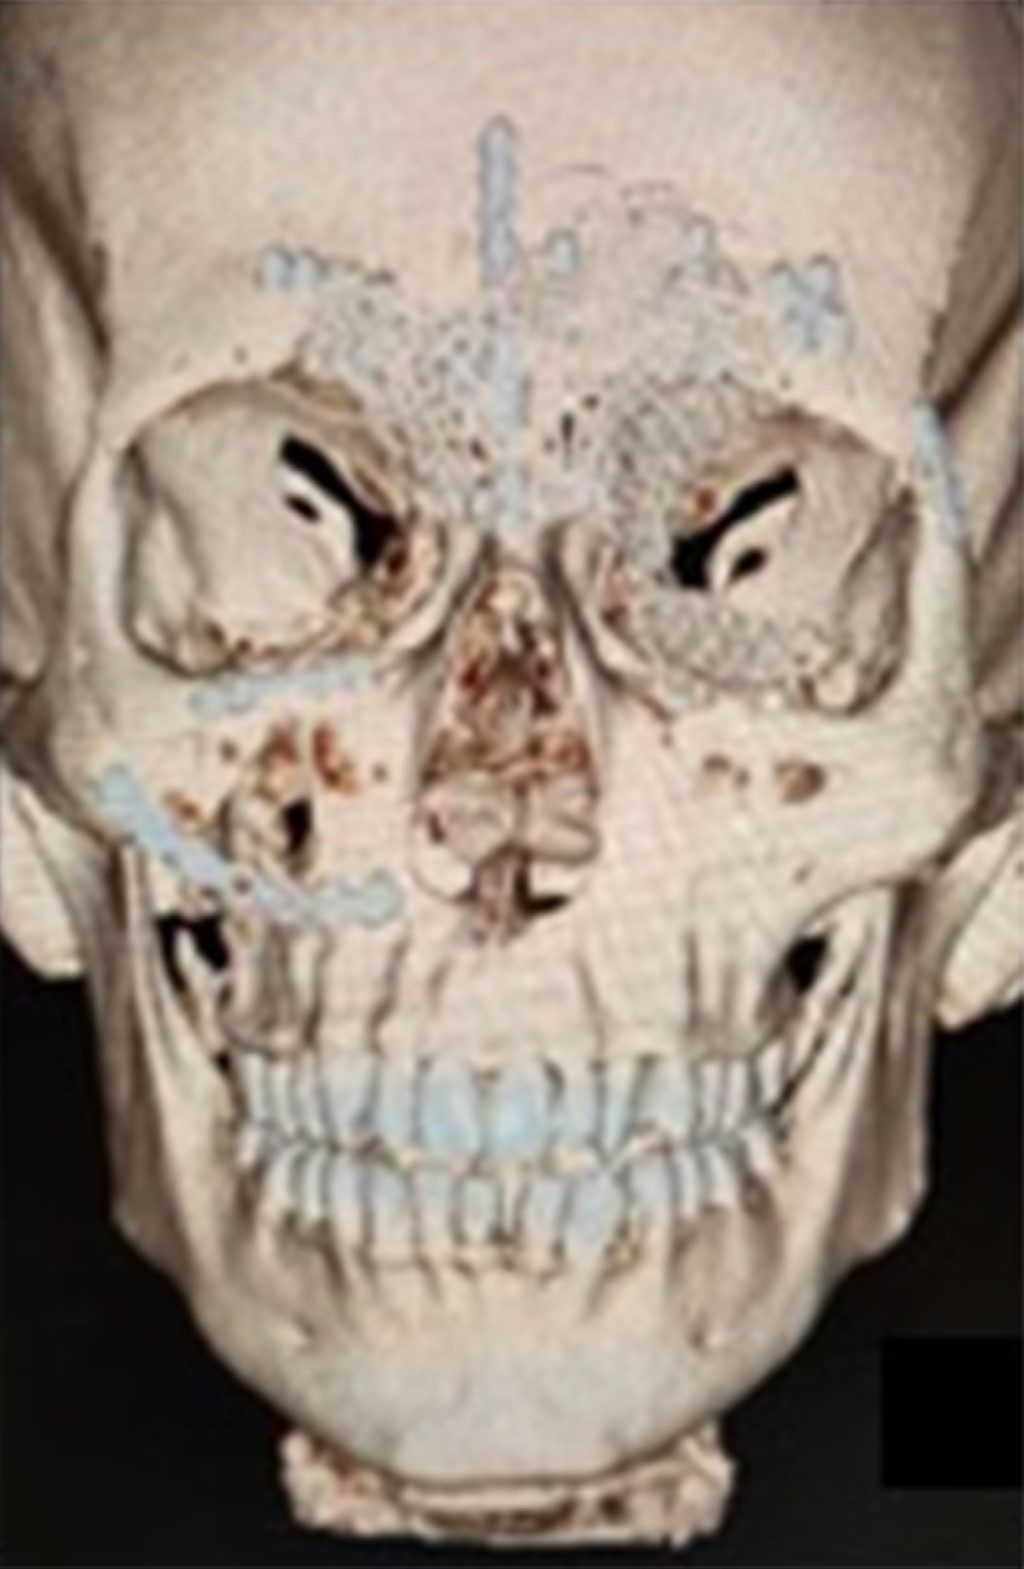

Una tomografía computarizada de la cara mostró una fractura de tipo Le Fort I del suelo, de la pared medial y del techo orbitario bilateral, fractura del cigomático derecho y de la pared anterior del hueso frontal.

Bajo anestesia general, el paciente fue intervenido cinco días después del traumatismo para la reducción y fijación de las fracturas realizando un acceso bicoronal (Figura 1), infraciliar bilateral, sutura frontozigomática del lado izquierdo y acceso intraoral de Caldwell-Luc en fondo del saco superior del lado derecho. Las fracturas orbitarias bilaterales se reconstruyeron con malla de titanio en el suelo, la pared medial y el techo orbitario; todas las fracturas se fijaron con placas y tornillos del sistema de 1.5 mm; se realizó una prueba de ducción forzada con pinzas Adson y la movilidad del globo terráqueo fue satisfactoria (Figura 2).

En la tomografía computarizada postoperatoria de la cara se puede observar la reconstrucción de las fracturas del seno frontal, del techo, de la pared medial y del suelo orbitario y sus respectivas fijaciones (Figuras 3 y 4).